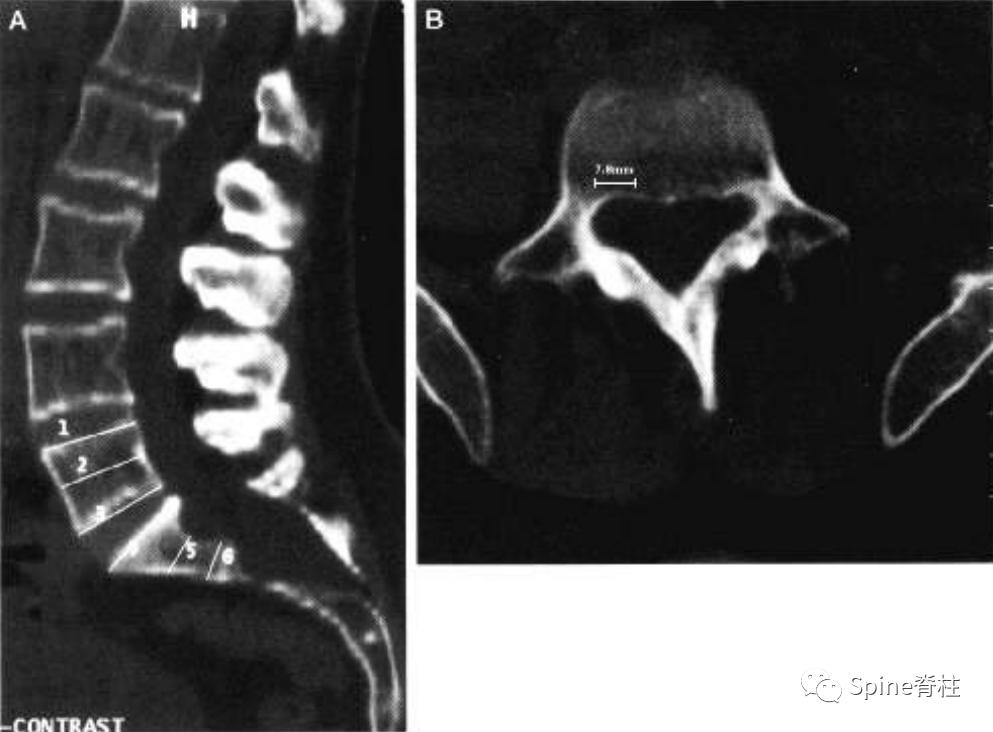

一位马凡综合征伴硬膜扩张患者的CT图像。a为正中矢状位重建,可见S2的椎管宽度大于L4。S1扇形缺损值为4.2mm。b为L5水平的横断面提示一个神经根袖的直接为6.6mm。因此,这个患者满足一个主要标准和两个次要标准。

一个马凡综合征伴硬膜扩张患者的MRI。a为T2正中矢状位提示S2硬膜囊的宽度大于L4,存在骶骨前硬膜膨出,S1的扇形缺损值为5.1。c为横断面提示一个神经根袖直径>7.0mm。因此,这个患者满足两个主要标准和两个次要标准。